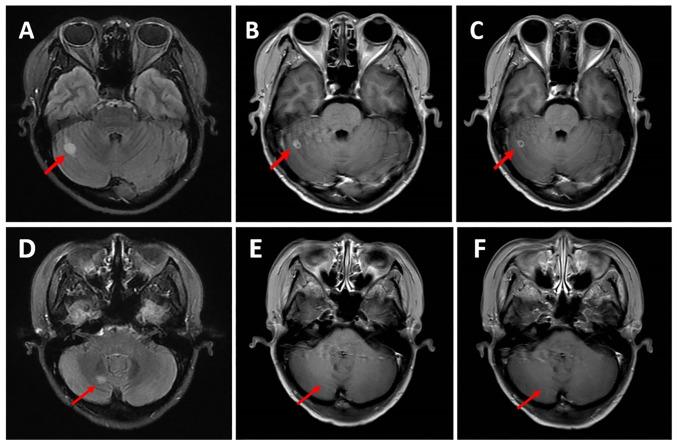

For patients with hormone receptor-positive (HR) and human epidermal growth factor receptor 2-negative (HER2) metastatic breast cancer (mBC), the treatment choices become more complex after progression on first-line CDK4/6 inhibitors combined with endocrine therapy. Currently, there are no guidelines that provide a unified standard protocol for this situation. Almost half of patients with mBC develop brain metastases (BMs), and once BMs occur, the survival of the patient is often significantly reduced. An anti-angiogenic drug and chemotherapy combination of has demonstrated synergistic effects in an mBC cell line. Anti-angiogenic drugs have shown therapeutic efficacy in the treatment of mBC, and utidelone has shown the ability to cross the blood-brain barrier and achieve a high concentration in brain tissue in preclinical studies. The present case report describes a patient with HR/HER2 mBC and BMs that developed resistance to two CDK4/6 inhibitors and treatments with anthracyclines/taxanes. The patient received a fourth-line treatment regimen combining utidelone with a small-molecule anti-angiogenic drug, namely apatinib or anlotinib. The patient achieved a partial response with this combined regimen, and a progression-free survival (PFS) of 7.6 months, which was the best therapeutic outcome in the entire course of the illness. This result was superior to the second-line treatment with nab-paclitaxel, which resulted in a PFS of 8 months and best overall response of stable disease with slight shrinkage. The present case indicates that a combination of utidelone with apatinib/anlotinib exhibited antitumor activity in a patient with HR/HER2 mBC with BMs. Therefore, this combination offers a promising therapeutic option for the clinical treatment of patients with breast cancer and BMs.

对于激素受体阳性(HR)且人表皮生长因子受体2阴性(HER2)的转移性乳腺癌(mBC)患者,在一线CDK4/6抑制剂联合内分泌治疗进展后,治疗选择变得更加复杂。目前,尚无指南针对这种情况提供统一的标准方案。几乎一半的mBC患者会发生脑转移(BMs),一旦发生BMs,患者的生存期通常会显著缩短。抗血管生成药物与化疗联合在一种mBC细胞系中已显示出协同作用。抗血管生成药物在mBC治疗中已显示出治疗效果,在临床前研究中,优替德隆已显示出能够穿过血脑屏障并在脑组织中达到高浓度。本病例报告描述了一名患有HR/HER2 mBC和BMs的患者,该患者对两种CDK4/6抑制剂以及蒽环类/紫杉类治疗产生了耐药性。该患者接受了优替德隆与小分子抗血管生成药物(即阿帕替尼或安罗替尼)联合的四线治疗方案。该联合方案使患者获得了部分缓解,无进展生存期(PFS)为7.6个月,这是整个病程中的最佳治疗结果。该结果优于二线白蛋白结合型紫杉醇治疗,后者的PFS为8个月,最佳总体反应为疾病稳定且有轻微缩小。本病例表明,优替德隆与阿帕替尼/安罗替尼联合在一名患有HR/HER2 mBC和BMs的患者中表现出抗肿瘤活性。因此,这种联合为乳腺癌和BMs患者的临床治疗提供了一种有前景的治疗选择。